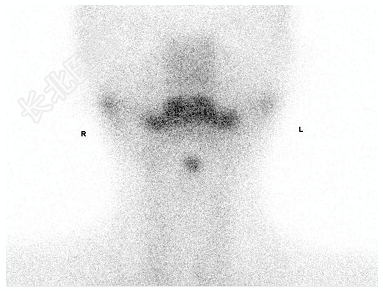

- [材料题] 女性,12岁,发现颈部正中无痛性包块1年,行⁹⁹TcᵐO₄⁻甲状腺显像如图。

- 简答题1、该患者诊断是?

- 简答题2、与哪些疾病进行鉴别?

- 简答题3、简述⁹⁹TcᵐO₄⁻甲状腺显像的原理和临床应用价值。

- 简答题4、阐述如何通过甲状腺显像定量分析来辅助诊断甲状腺疾病。